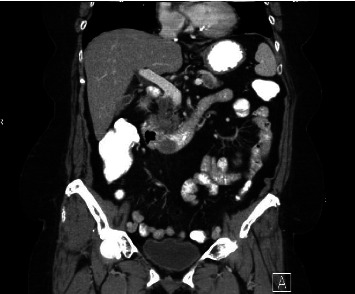

结直肠癌转移到十二指肠是非常罕见的,并提出了重大的诊断和治疗挑战。我们描述了一位68岁的女性右结肠腺癌患者,尽管接受了FOLFOX化疗,但仍发生了十二指肠转移。向FOLFIRI的过渡取得了有限的成功,强调了创新方法的必要性。遗传分析显示KRAS G12D突变,针对该突变的靶向治疗尚未获批。免疫组织化学证实十二指肠肿块起源于胃肠道。文献表明,手术切除可以提供治疗潜力,在某些情况下,虽然它是不可行的。新兴的kras靶向药物,如MRTX1133,代表了解决这种突变的有希望的选择。该病例强调了管理罕见转移模式的挑战,个性化治疗的潜力,以及进一步研究晚期结直肠癌创新治疗的必要性。它强调了制定有针对性的策略来改善这种复杂转移性疾病患者预后的重要性。

Metastasis to the duodenum from colorectal cancer is exceptionally rare and presents significant diagnostic and therapeutic challenges. We describe a 68-year-old female with right colon adenocarcinoma, who developed a duodenal metastasis despite treatment with FOLFOX chemotherapy. Transition to FOLFIRI yielded limited success, emphasizing the need for innovative approaches. Genetic analysis revealed a KRAS G12D mutation, for which targeted therapies are not yet approved. Immunohistochemistry confirmed the gastrointestinal origin of the duodenal mass. Literature indicates that surgical resection can offer curative potential in select cases, although it was not viable here. Emerging KRAS-targeted agents, such as MRTX1133, represent promising options for addressing this mutation. This case underscores the challenges of managing rare metastatic patterns, the potential of personalized therapies, and the necessity for further research into innovative treatments for advanced colorectal cancer. It highlights the importance of developing targeted strategies to improve outcomes for patients with such complex metastatic diseases.